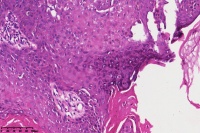

脂溢性角化症伴皮角?

性别

女

年龄

49岁

手臂皮肤组织

图3

脂溢性角化病